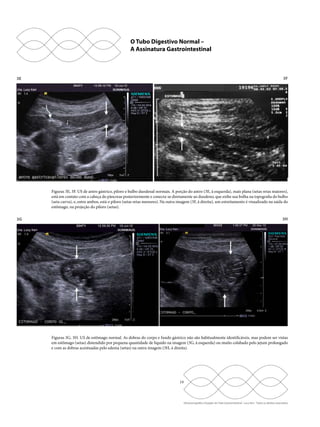

Figuras 3A, 3B. US de junção esôfago-gástrica. É mostrada em longitudinal (3A, à esquerda) e em transversal (3B, à direita), ambas assi-naladas

com seta e mostrando o lúmen com partículas gasosas mescladas com muco na região central da estrutura. Observar que, em 3A, é

possível identificar a continuidade da junção esôfago-gástrica (setas) com o estômago, que contém líquido no seu interior.

Figuras 3C, 3D. US de fundo e corpo gástrico. A imagem (3C, à esquerda) mostra o fundo gástrico junto aos segmentos 2 e 3 do lobo es-querdo

do fígado, em secção longitudinal, e corpo gástrico distendido por líquido no hipocôndrio esquerdo (3D, à direita).